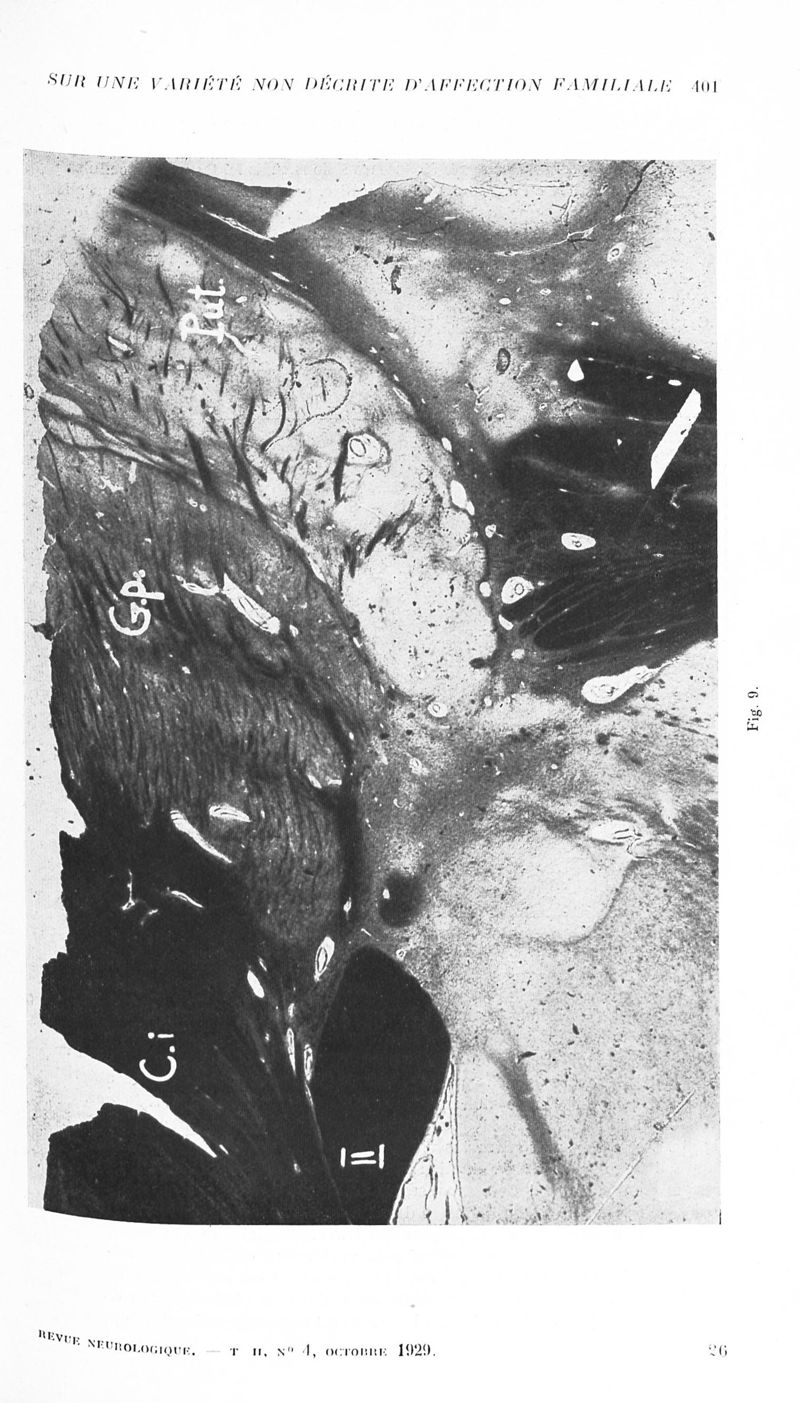

Revue neurologique

1929, vol 2. - Paris : Masson , 1929.